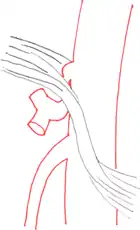

Further evaluation and confirmation can be obtained via angiography to investigate the anatomy of the celiac artery.[5] Historically, conventional angiography was used, although this has been largely replaced by less invasive techniques such as computed tomography (CT) and magnetic resonance (MR) angiography.[2][5] Because it provides better visualization of intra-abdominal structures, CT angiography is preferred to MR angiography in this setting.[5] The findings of focal narrowing of the proximal celiac artery with poststenotic dilatation, indentation on the superior aspect of the celiac artery, and a hook-shaped contour of the celiac artery support a diagnosis of MALS.[2] These imaging features are exaggerated on expiration, even in normal asymptomatic individuals without the syndrome.[2]

Proximal celiac artery stenosis with poststenotic dilatation can be seen in other conditions affecting the celiac artery.[2] The hook-shaped contour of the celiac artery is characteristic of the anatomy in MALS and helps distinguish it from other causes of celiac artery stenosis such as atherosclerosis.[2] This hooked contour is not entirely specific for MALS however, given that 10–24% of normal asymptomatic individuals have this anatomy.[2]

Median arcuate ligament syndrome-a)Stenosis and aneurysm of celiac artery because of compression arrows b)severe stenosis and poststenotic dilatation white arrow c) median arcuate ligaments arrows and gastric mucasal thickening -

Coeliacus compression